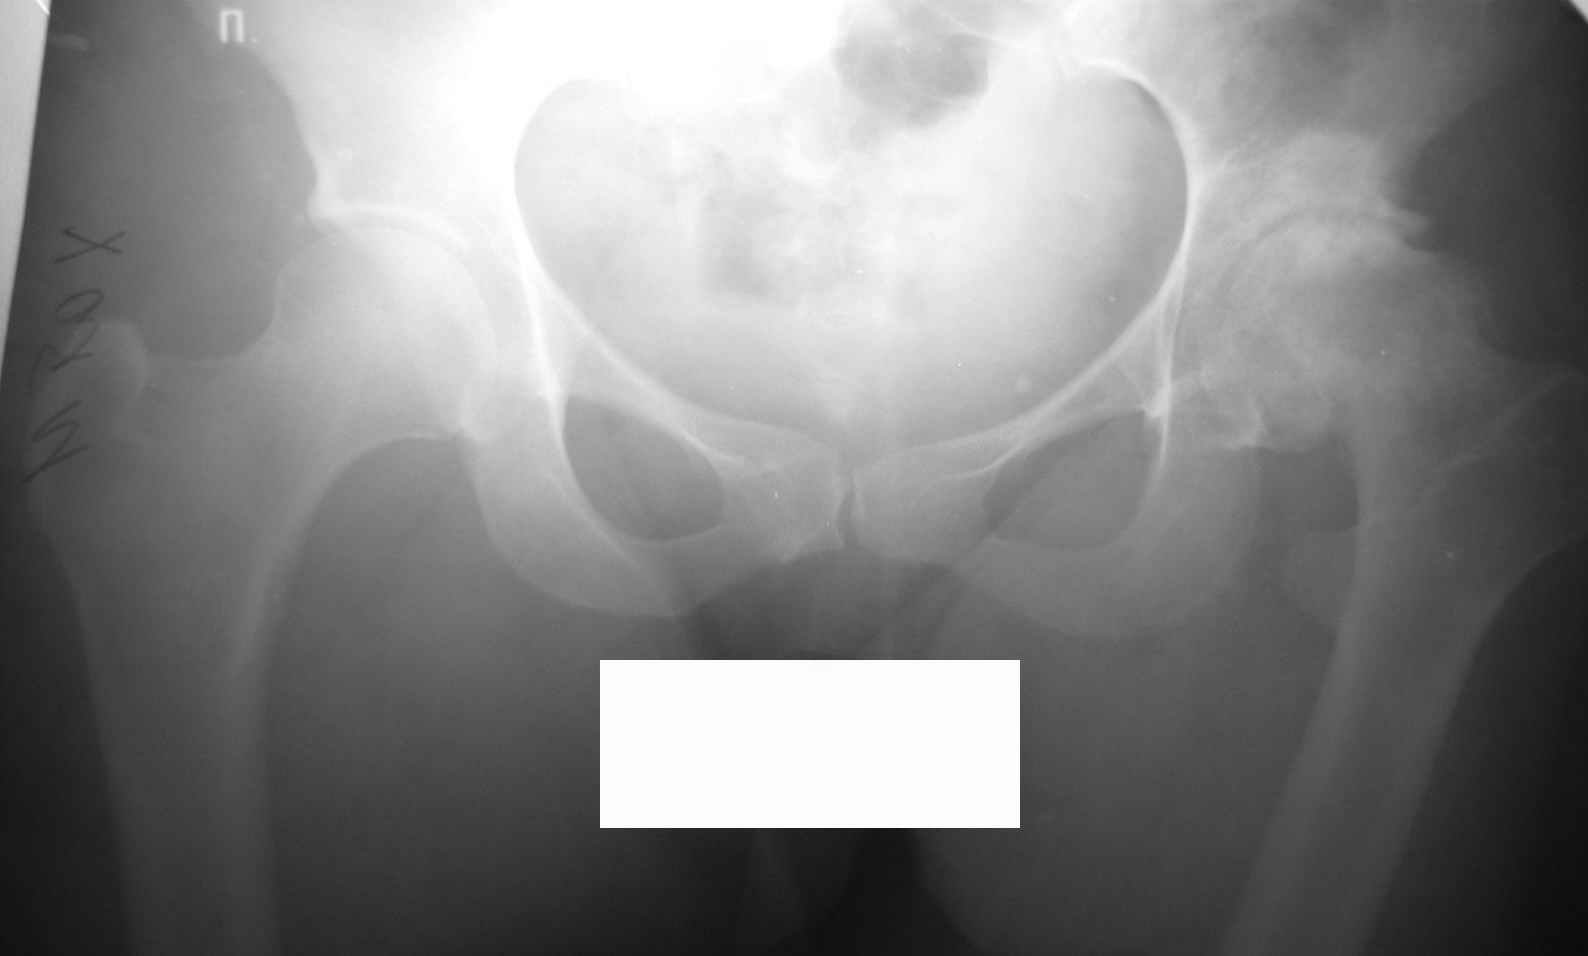

Извините, Анатолий, головка не выглядит потерянной, укорочение 5 см из-за порочного положения. Подход у молодой женщины я бы выбрал в зависимости от мобильности сустава.

На ригидном суставе межвертельная остеотомия для женщины мало привлекательна, но при гипомобильности, а тем более мобильности сустава вполне пригодна. И эффект от операции мы наблюдаем больше 10 лет и для последующего эндопротезирования трудности не велики, если остеотомию правильно спланировать и выполнить (проксимальный отдел бедра после остеотомии должен соответствовать нормальной анатомической геометрии). Привожу, что под рукой - Ртг 1997 ( даме 27 лет) и 2004 года. А моделей эндопротезов бесцементной фиксации для такой рентгеноантомической формы коксартроза действительно достаточно.

ВВП, МОНИКИ

Кликните для загрузки файла Форум.jpg

68KB (69817 bytes)